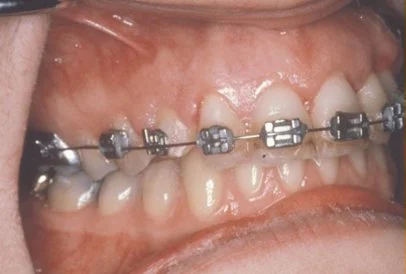

In cases where the eyeteeth will not erupt spontaneously, the orthodontist and oral surgeon will work together to get these teeth to erupt. Each case must be evaluated on an individual basis, but treatment will usually involve a combined effort between the orthodontist and the oral surgeon. The most common scenario will call for the orthodontist to place braces on the teeth (at least the upper arch). A space will be opened to provide room for the impacted tooth to be moved into its proper position in the dental arch. If the baby eyetooth has not fallen out already, it is usually left in place until the space for the adult eyetooth is ready. Once the space is ready, the orthodontist will refer the patient to the oral surgeon to have the impacted eyetooth exposed and bracketed.

In a simple surgical procedure performed in the surgeon’s office, the gum on top of the impacted tooth will be lifted up to expose the hidden tooth underneath. If there is a baby tooth present it will be removed at the same time. Once the tooth is exposed, the oral surgeon will bond an orthodontic bracket to the exposed tooth. The bracket will have a miniature gold chain attached to it. The oral surgeon will guide the chain back to the orthodontic arch wire where it will be temporarily attached. Sometimes the surgeon will leave the exposed and impacted tooth completely uncovered by suturing the gum up high above the tooth, or making a window in the gum covering the tooth. Most of the time the gum will be returned to its original location and sutured back with only the chain remaining visible as it exits a small hole in the gum.

Shortly after surgery (1-14 days) the patient will return to the orthodontist. A rubber band will be attached to the chain to put a light eruptive pulling force on the impacted tooth. This will begin the process of moving the tooth into its proper place in the dental arch. This is a carefully controlled, slow process that may take up to a full year to complete. Remember, the goal is to erupt the impacted tooth and not to extract it. Once the tooth has moved into the arch in its final position, the gum around it will be evaluated to make sure it is sufficiently strong and healthy to last for a lifetime of chewing and tooth brushing. In some circumstances, especially those where the tooth had to be moved a long distance, there may be some minor “gum surgery” required to add bulk to the gum tissue over the relocated tooth so that it remains healthy during normal function. Your dentist or orthodontist will explain this procedure to you if it applies to your specific situation.